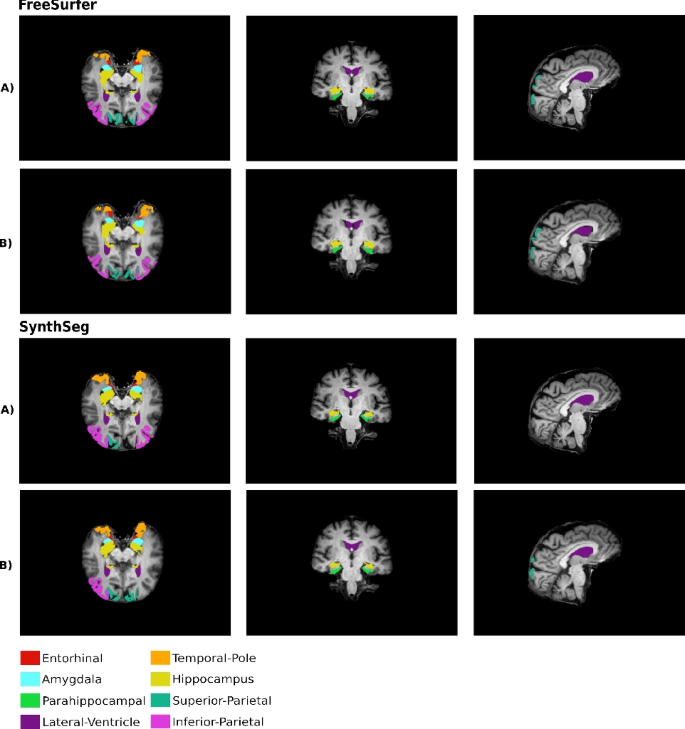

Figure 3 demonstrates consistency with the observed results, where the performance of FreeSurfer was generally inferior. In particular, the right temporal pole label (for the considered slice) is not segmented by this tool in the case of the accelerated sequence, which agrees with the results showing this region had the lowest Dice coefficient values.

Axial (left), coronal (middle), and sagittal (right) views illustrating the volumetric segmentation of 16 chosen structures, color-coded according to the legend. First two rows present FreeSurfer segmentation, last two rows SynthSeg. (A) identifies segmentation obtained from the conventional T1w sequences, while (B) from the accelerated one.